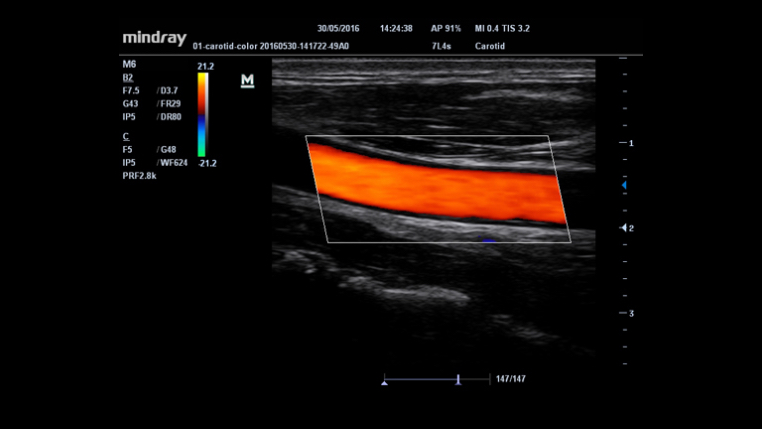

IMT(Intima-Media Thickness)

?? ? ?? ? ?? ? ??? ?? ???? ??? ???? ??? ?????.

Smart Track

?????? ??? ??: ??? ??? ????? ???? ??? ???? ??? ?? ?? ??? ??? ??????.